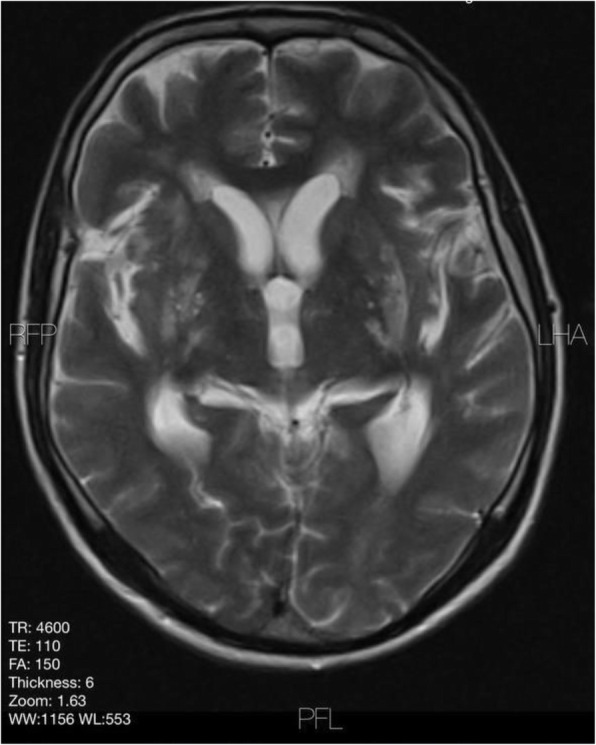

Background and purpose: Although the majority of migraine with aura (MwA) patients experience simple visual aura, a discrete percentage also report somatosensory, dysphasic or motor symptoms (the so-called complex auras). The wide aura clinical spectrum led to an investigation of whether the heterogeneity of the aura phenomenon could be produced by different neural correlates, suggesting an increased visual cortical excitability in complex MwA. The aim was to explore whether complex MwA patients are characterized by more pronounced connectivity changes of the visual network and whether functional abnormalities may extend beyond the visual network encompassing also the sensorimotor network in complex MwA patients compared to simple visual MwA patients.

Methods: By using a resting-state functional magnetic resonance imaging approach, the resting-state functional connectivity (RS-Fc) of both visual and sensorimotor networks in 20 complex MwA patients was compared with 20 simple visual MwA patients and 20 migraine without aura patients.

Results: Complex MwA patients showed a significantly higher RS-Fc of the left lingual gyrus, within the visual network, and of the right anterior insula, within the sensorimotor network, compared to both simple visual MwA and migraine without aura patients (p < 0.001). The abnormal right anterior insula RS-Fc was able to discriminate complex MwA patients from simple aura MwA patients as demonstrated by logistic regression analysis (area under the curve 0.83).

Conclusion: Our findings suggest that higher extrastriate RS-Fc might promote cortical spreading depression onset representing the neural correlate of simple visual aura that can propagate to sensorimotor regions if an increased insula RS-Fc coexists, leading to complex aura phenotypes.

Fig. 1 (abstract A20).

See text for description.